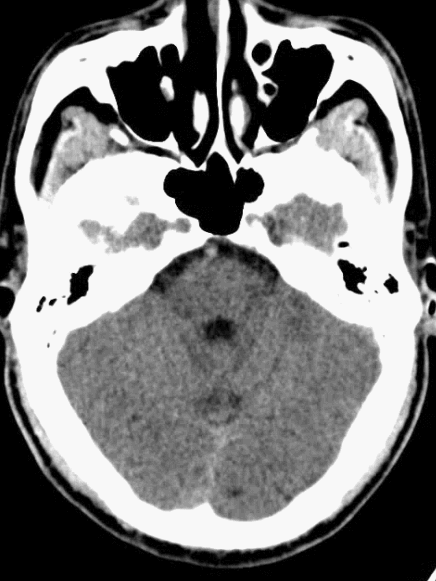

术前影像学检查

我院急查头颅CTP示:ASPECT评分10分。

DSA: